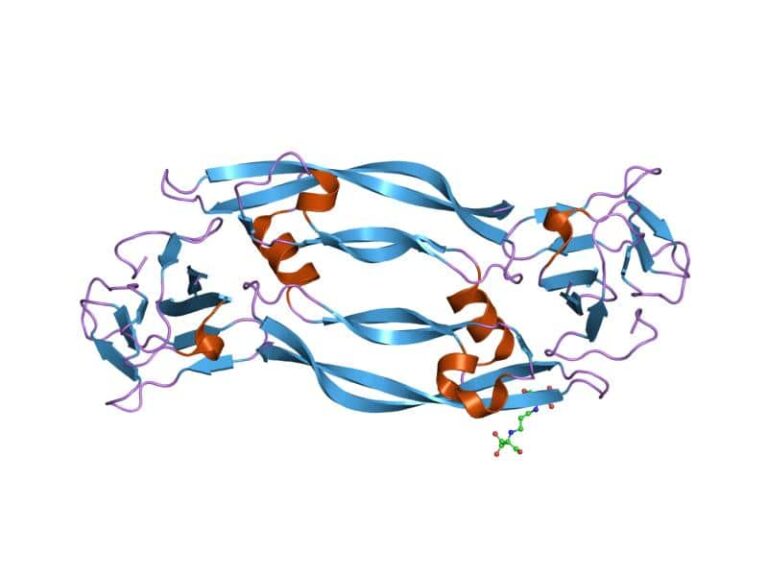

Concentração sérica materna do fator de crescimento placentário entre 11-13 semanas em gestações com anomalias cromossomicas

Trabalho do realizado no King’s College que correlaciona a concentração sérica materna do fator de crescimento plancentário (PIGF)…